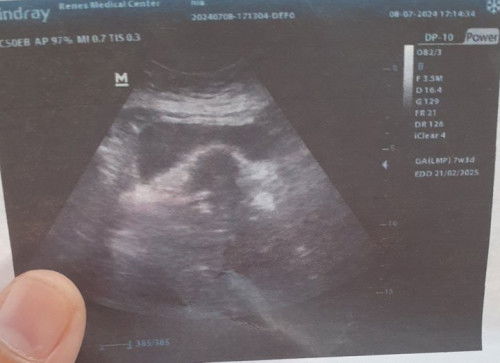

sharing yah bun hppt 17 mei telat 1 hari tespek positif langsung ke dokter kandungan hasilnya msih penebalan rahim lanjut 2 minggu kemudian kontrol udh ada kantung sempat kepikiran apa hamil ksoong untuk mengatasi kecemasan tepat hari ini kontrol hasil usg 7minggu hamil ga ngerasa apa² sehat2 yah buat kita semua bunda diberi kelancaran dan yg msih jdi pejuang garis 2 tetap semangat waktu Tuhan pasti yang tepat dan terbaik😇😇😇 ##Sharing_dong_Bund